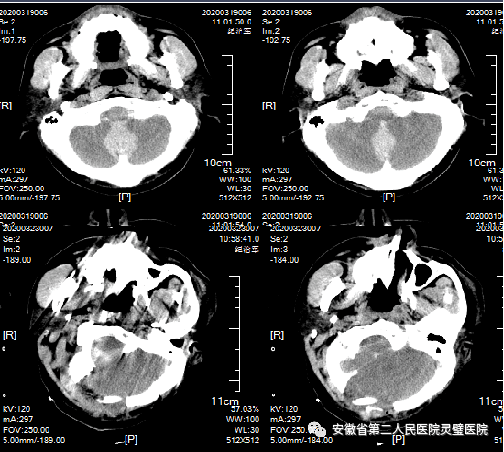

一、颅脑创伤个体化精准救治技术

颅脑创伤是神经外科常见病、多发病,近十年来,我们成功诊治了大量重型颅脑损伤患者,尤其在特重型颅脑损伤、原发性脑干伤、弥漫性轴索损伤等方面积累了丰富的经验,并形成了以“神经多模态监测、亚低温治疗、镇静镇痛、大骨瓣减压以及精准化脑保护”等核心技术为特色的一体化标准化救治方案,重型颅脑创伤患者死亡率逐年降低,达到国内一流水平。

硬膜下血肿、脑挫裂伤术前和术后 颅内压监测

大骨瓣减压术治疗硬膜下血肿及切口

后颅窝及小脑半球外伤手术前后

重型颅脑损伤(GCS 3分),脑疝,个体化切口设计